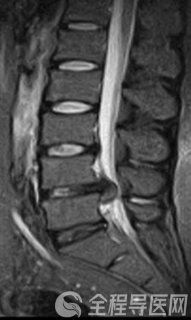

8月上旬的一天,急诊送来了一名胸痛、大汗、心律失常的七旬老人。徐州矿务集团总医院心内科主任祁春梅接诊后为老人做了检查,心电图结果表明,老人有3支右侧心脏血管病变,左心室前降支与回旋支闭塞。判断老人是心急性心梗,情况十分危急。祁主任立刻与家属沟通,建议立即为老人采取手术开通血管。随后经过严密的准备,老人被送入导管室做造影明确病变部位。而造影后的结果却令在场医生震惊,因为老人的左主干在这段时间内竟然发生了病变,全部堵塞!手术台上,老人已经明显感觉更加难受,整个人烦躁、胸闷、十分痛苦。

祁主任立即又与家属进行了二次谈话,阐明了各种利害关系,并说服六神无主的家属立即为老人做左主干开通手术,与生命抢时间。就是在这样的一个突发状况下,祁春梅和她的团队凭借精湛的技术、沉稳的心态、紧密的合作,仅用15分钟就为老人开通了左主干血管,并在接下来陆续开通前降支、回旋支血管,使病人转危为安。